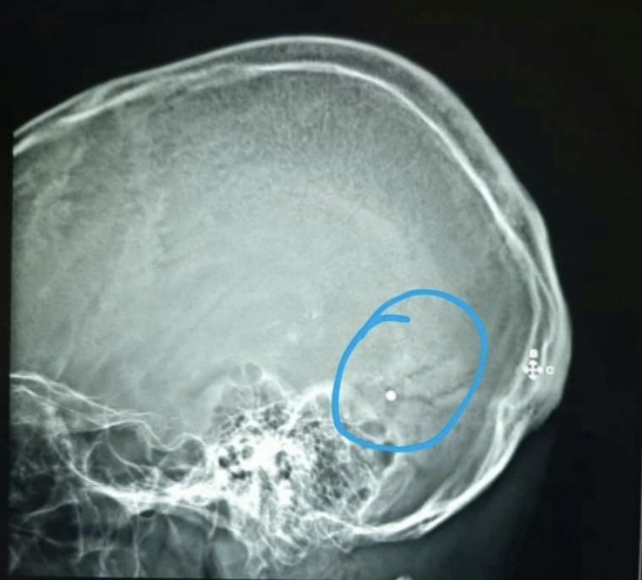

Chakhtoura said his colleague Dr Elie Saliba had been shot in the head at Saturday’s protests after working long shifts to save victims of the Beirut explosion.